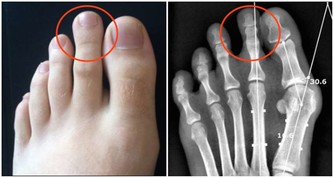

惡性黑色素瘤是皮膚癌的一種,雖然在中國還不是很常見,但是在歐美地區卻是常見的惡性腫瘤之一。在我國不常見並不意味著黑痣對人體是無害的,近幾年來皮膚癌在我國的發病率也逐漸升高,所以我們還是需要了解其產生的原因,事先做好防護措施,防患於未然。 為什麼說腳趾上的黑痣更容易演變成癌症因子呢?因為黑痣在正常情況下癌變的機率是比較小的,但是如果經常遇到摩擦、擠壓,將會增大其癌變的可能性。我們的腳趾常年處於摩擦和擠壓的狀態下,所以更加容易造成癌變。 黑痣本身就是我們身體與生俱來的良性腫瘤。後天由於生活環境的影響以及自身各個器官的病變,導致了其進一步惡化為黑色素瘤。 還有一部分認為,黑痣只有在暴曬的情況下才會演變成黑色素瘤,但是我們正常情況下是不會暴曬到腳趾部位的。所以我們會容易忽略掉腳趾上的「癌症病毒」。但是,作為皮膚癌中最危險的黑色素瘤,是非常容易發展到不經常接觸陽光的部位。黑素瘤甚至可能出現在腳趾甲下面,看起來就像是一個普通的黑點。 所以如果腳趾部位出現黑痣的話,請大家要做好保護措施,經常觀察黑痣是否有異常變化,如果出現異常請儘快就醫。 3、勺子狀的腳指甲 有時對指甲的傷害或是長期接觸石油基質溶劑可能造成凹陷的像勺子一樣的腳趾形狀。同時,缺鐵也可能會形成這種特殊形狀。